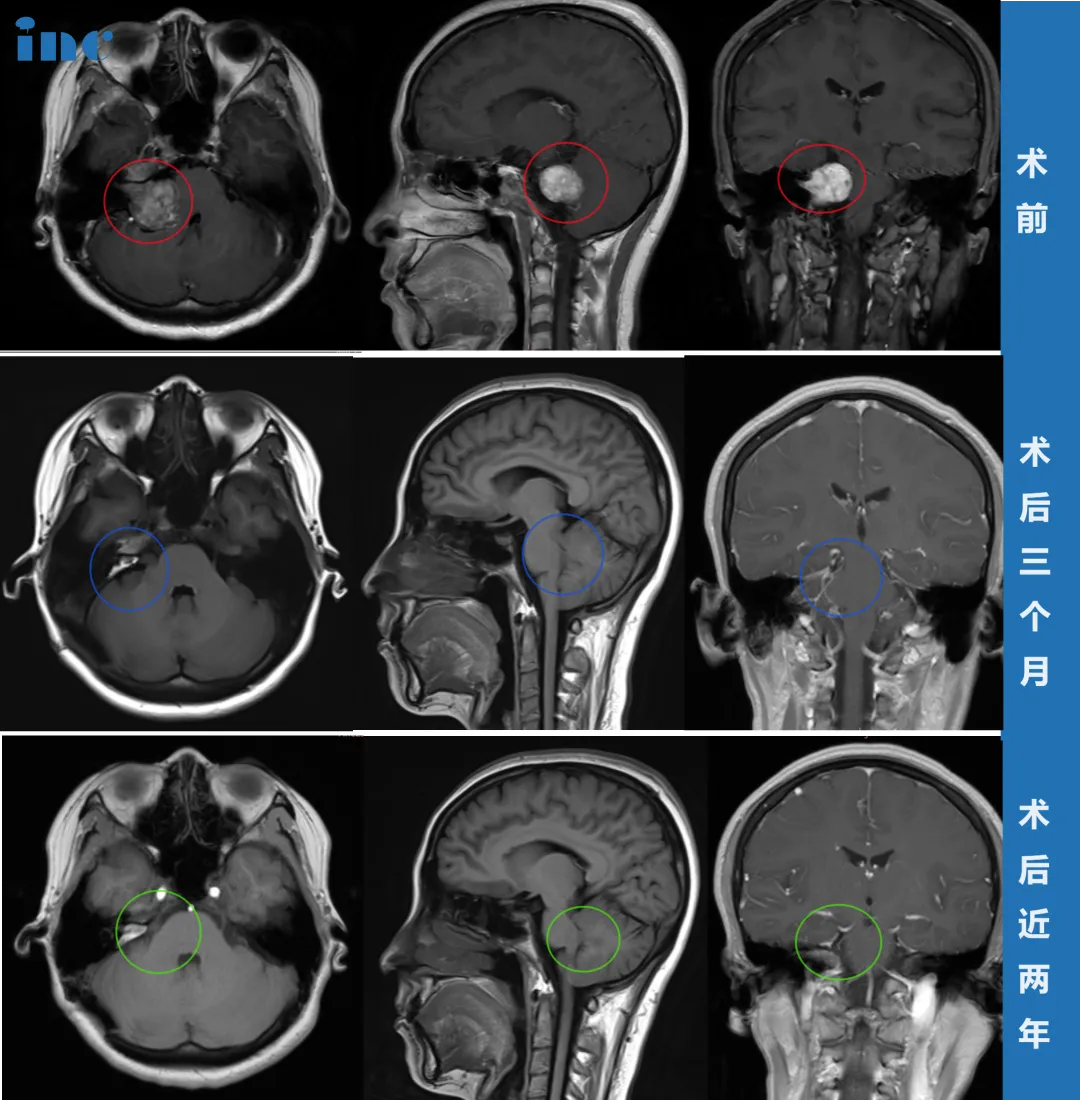

这次,她做了头颅核磁共振(MRI)检查,结果终于揭示了病因——右侧CPA区前庭神经鞘瘤。肿瘤最大直径约35毫米(包括内听道内的部分),已经压迫到脑干,导致桥脑及右侧桥臂受压,四脑室变形。

一切准备就绪后,巴教授针对肿瘤的具体位置、形态特点,手术采用适合患者具体情况的个体化手术入路,术中使用神经电生理监测和MRI辅助,保证神经功能、重要脑组织不受损伤,在显微镜下完成并确认肿瘤全部切除。

令人欣慰的是,李女士术后当天即拔除气管插管,可完全自主唿吸。复查CT显示正常,无脑出血等并发症。

虽然术后因水肿出现了短暂面瘫,但经过积极康复锻炼,术后两个月基本恢复,半年后恢复良好。

术后两年MRI检查结果更让人满意:肿瘤被完全切除,没有任何复发迹象。如今她的面部功能完全恢复,面部对称,右侧面神经功能良好。